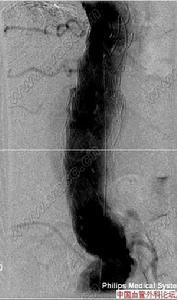

主動脈竇動脈瘤破裂7.逆行升主動脈造影可確診,表現為動脈竇擴大畸形,右心室流出道和肺動脈或右心房有造影劑顯影。

主動脈竇動脈瘤破裂主動脈竇動脈瘤是一種罕見的先天畸形,約占先天性心臟病患病率的2%~3.56%,其破入右室者最多,其次為右房。發生原因主要是胚胎期竇壁中層彈力纖維發育不良,在主動脈內高壓影響下,該薄弱處逐漸變薄擴張,呈囊袋狀突出,當壓力突然增加時破裂,由於主動脈和破入心腔間存在著較大的壓力階差,可產生大量的左向右分流,因而導致全心容量負荷增加,特別是外破口較大或破入右房者,病情進展快,容易發生充血性心力衰竭,部分患者易繼發心內膜炎、心律紊亂、腎功能衰竭等嚴重併發症。臨床多表現為起病急、進展快。一般認為,主動脈竇動脈瘤破裂之前多無明顯症狀和體徵,一旦破裂,即產生劇烈胸痛及顯著的血流動力學改變。破入右室、右房者可出現右心衰竭,呈進行性加重。體徵有胸骨左緣第3、4肋間連續性響亮機器樣雜音,常伴有肺動脈高壓、右心功能不全及脈壓差增大的表現。首次聽診往往有主動脈瓣受損的印象,易誤診為主動脈瓣關閉不全,本例即是此種情況。超聲心動圖是最佳的無創診斷法,可直接顯示主動脈竇動脈瘤的起源形態、突入的心腔位置、竇瘤破口大小、是否合併其他心臟畸形、分流的性質、時相、最大流速,提供血流動力學資料。一旦瘤體破裂,預後不良,可在數周至數月內因嚴重併發症死亡。內科治療只能起到短暫的減輕作用,手術治療往往可以獲得滿意的效果。該戰士因沒有及時手術,導致急性腎功能衰竭並時間過長,多臟器衰竭而死亡。